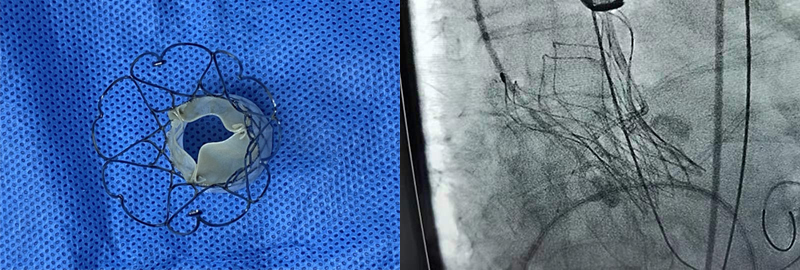

手术中

主动脉瓣膜 精准释放后X片